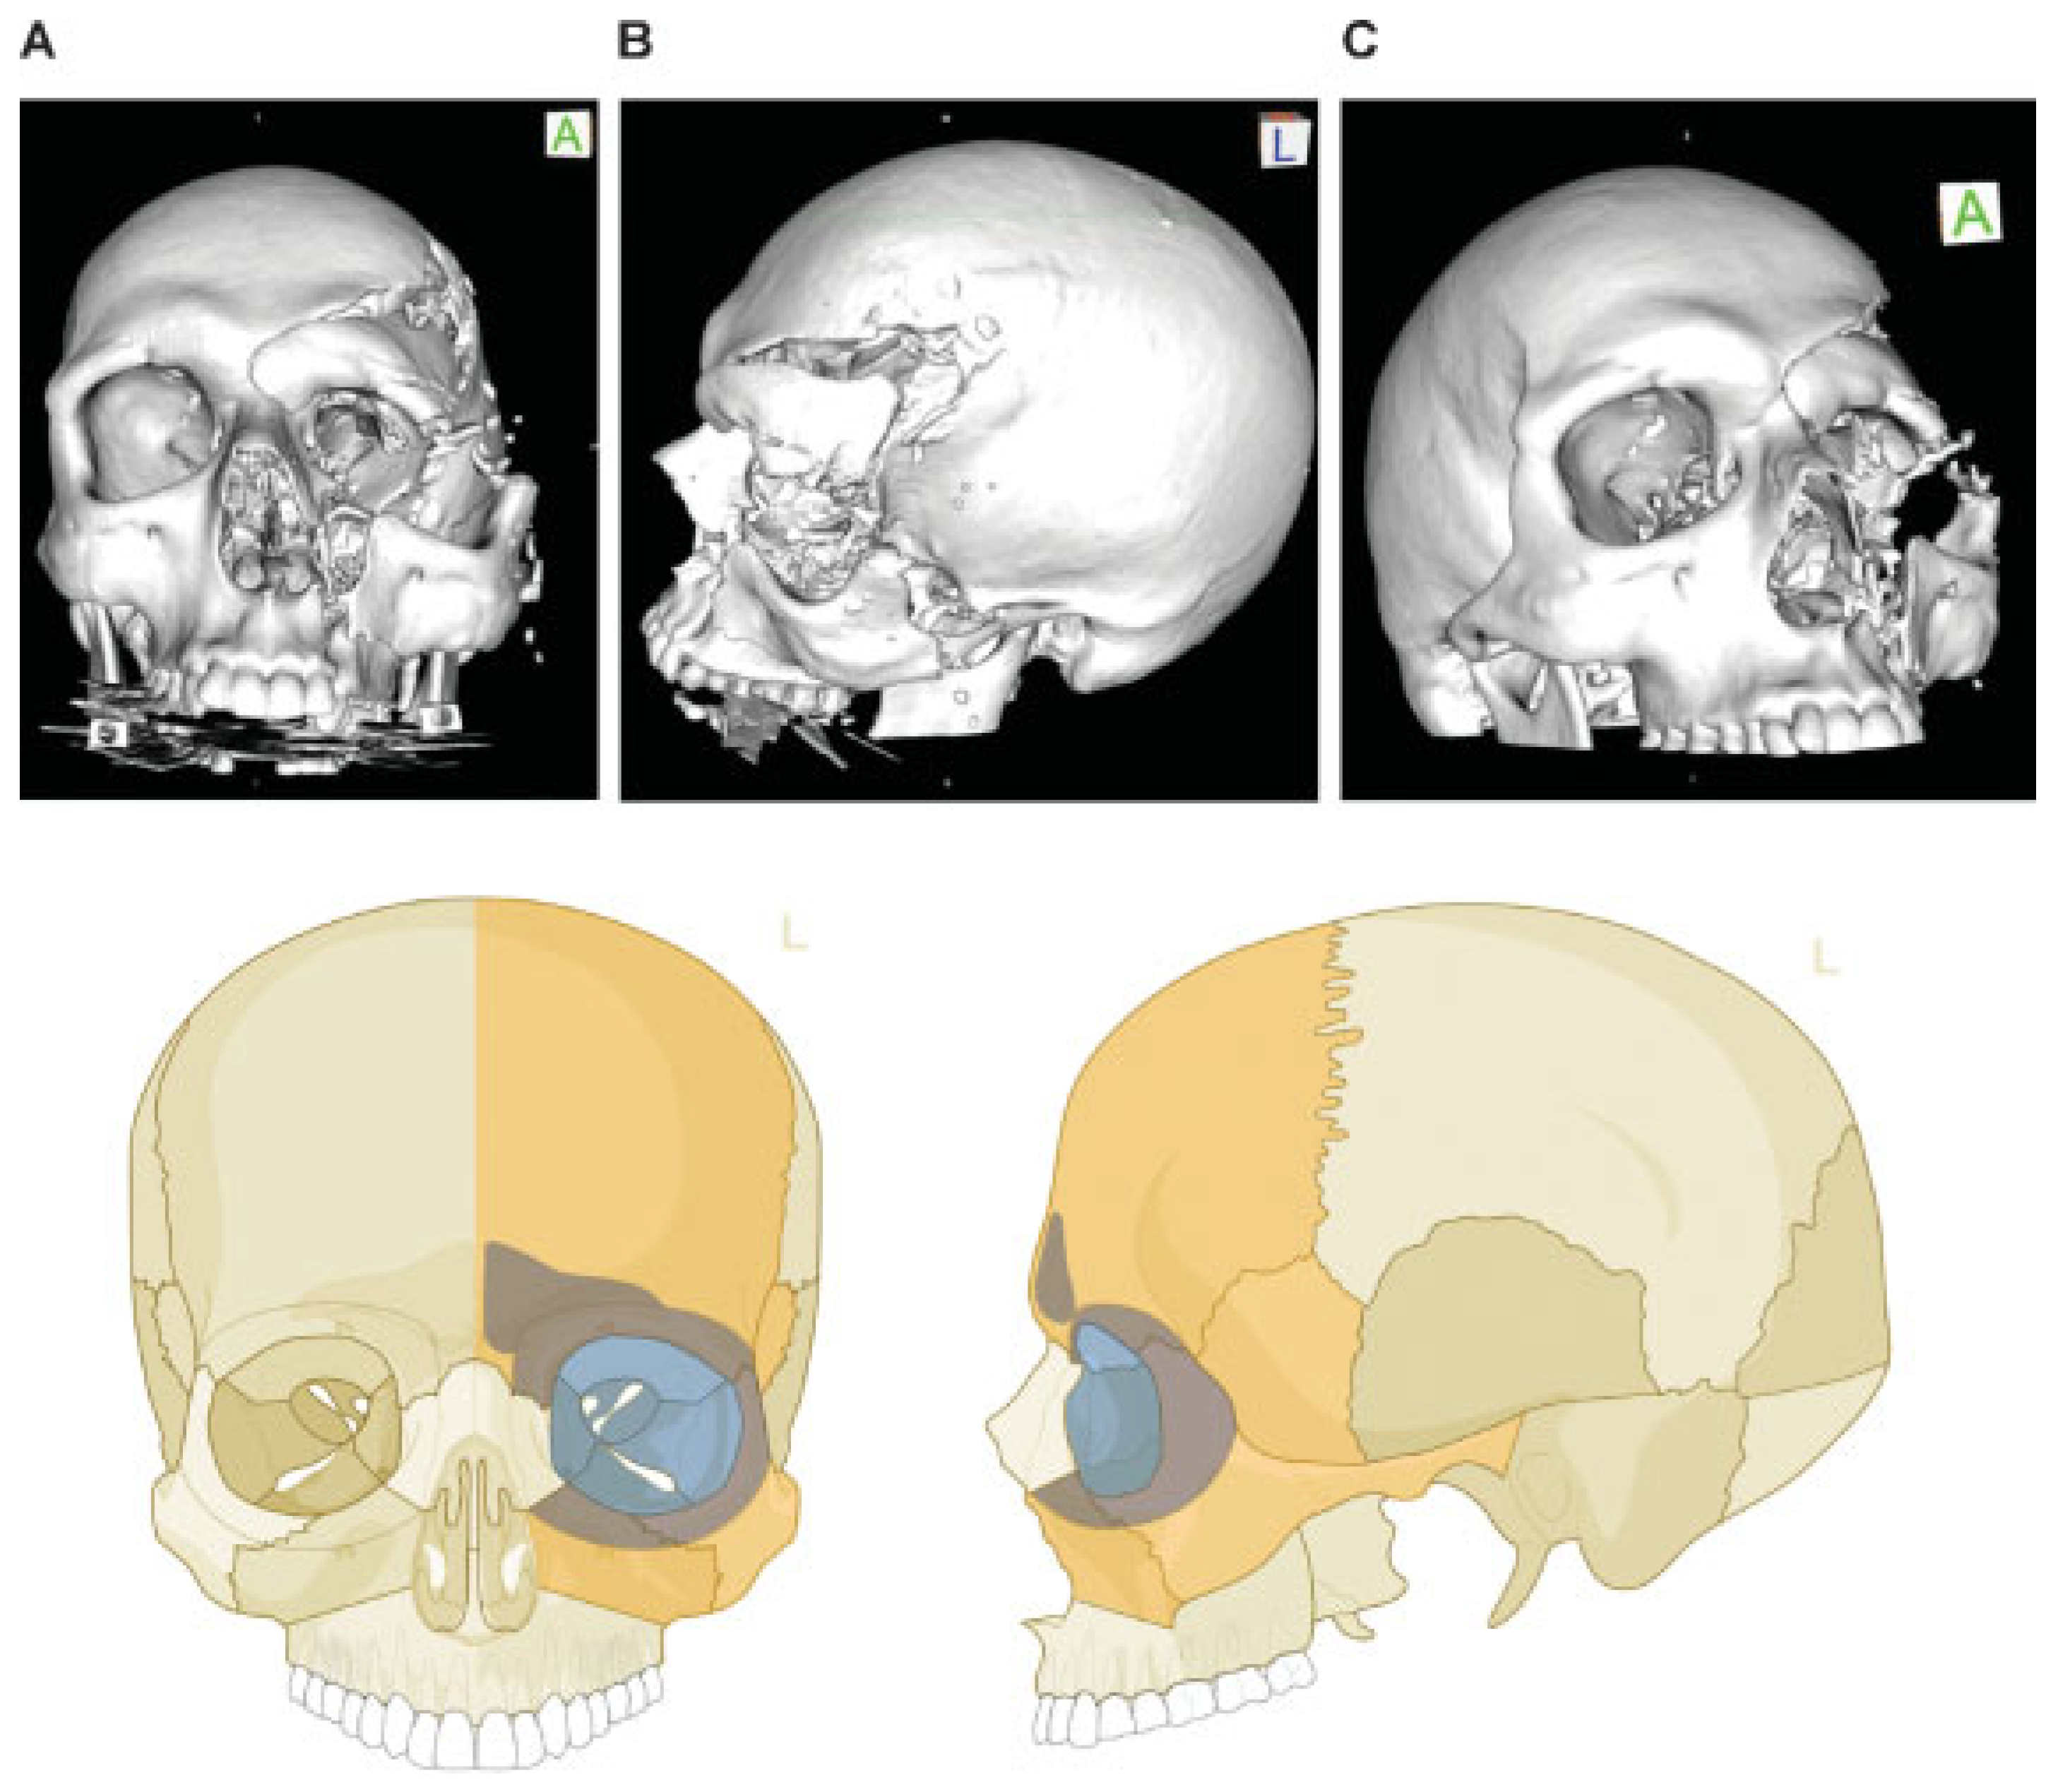

Figure 9.

Naso-orbito-ethmoidal fracture (Example 2)—NOE extreme Type III bilateral. Imaging: Three-dimensional (3D) computed tomographic scans (A) frontal view, (B) oblique lateral view right, and (C) oblique lateral view left. Narrative description: Medium-/small-sized fragments and extreme displacement (loss of interfragmentary contact) in a bilateral Naso Orbito Ethmoid Fracture in combination with a Le Fort I, II fracture, and left zyogma fracture. (D) Level 3 Code: 92 Z1i.I1i.L1.Pt0.Oim.U1m.Omil.Pt0.L1.I1i.Z1li - 93 m.M - 94 F1.m.F1m, Orbit (right): R(im).W1(im)2(im), Orbit (left): R(lim).W1(lim)2(lim). This case example CMTR-92-105 is made available electronically for viewing using the AOCOIAC software at www.aocmf.org/classification. Note: Involvement of midface and craniofacial transition as a consequence of fractures extending into the superomedial quadrants of the orbital rim - this is indicated by the marking of the entire frontal bone area.